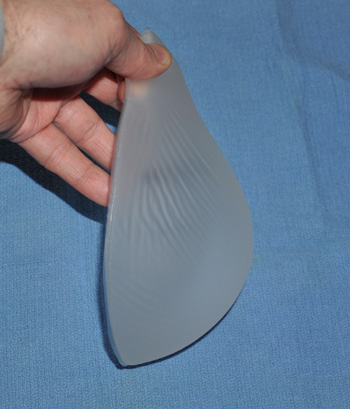

Анатомические импланты Eurosilicone

Раздел: Визуальный дайджест